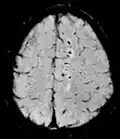

or "T2-star"

T2* Spoiled gradient recalled echo (GRE) with a long echo time and small flip angle[74] Low signal from hemosiderin deposits (pictured) and hemorrhages.[74]

Susceptibility-weighted SWI Spoiled gradient recalled echo (GRE), fully flow compensated, long echo time, combines phase image with magnitude image[75] Detecting small amounts of hemorrhage (diffuse axonal injury pictured) or calcium.[75]